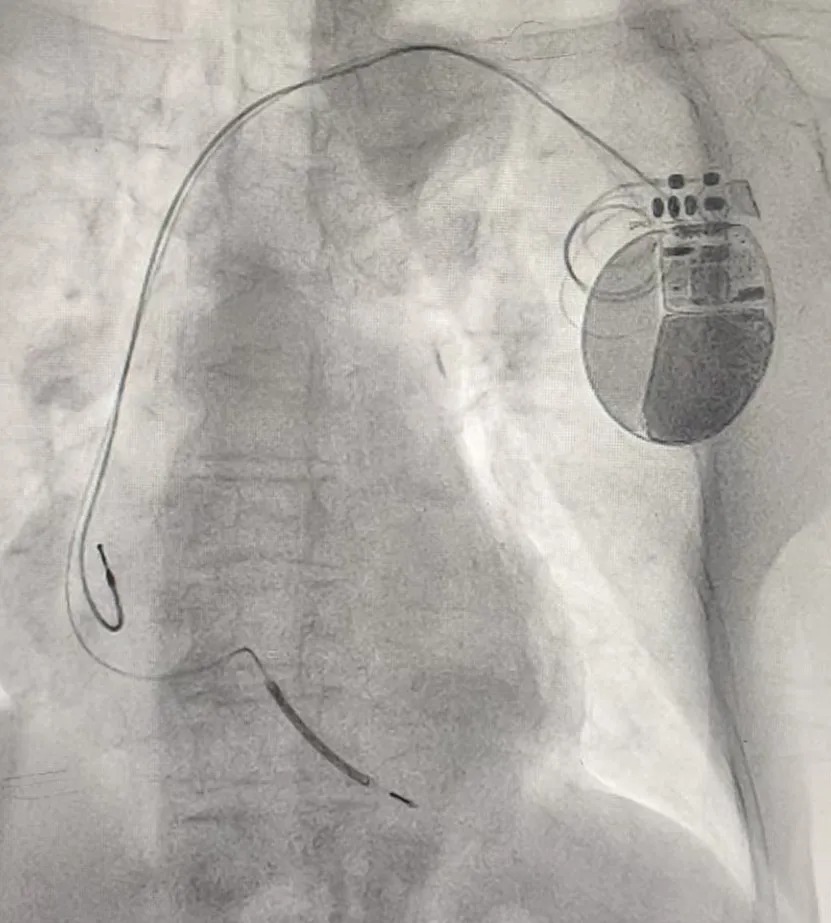

近日,滨州市中心医院入住一名年余90岁的晕厥老人,心血管内科一病区孙桂芳主任团队详细检查评估后,诊断为“室性心动过速”。结合患者身体状况,经充分讨论后,为其植入ICD治疗。

手术过程顺利,术后ICD功能监测各项指标正常,患者未再发作晕厥,现已康复出院,ICD给这位老人带来“心生”。该例ICD植入患者为医院首例,在全市范围内如此高龄患者成功植入ICD也较为罕见。

ICD是一种植入体内的小型电子医疗设备,植入在胸部皮下,电极导线连接到心脏,主要用于监测心脏节律,并检测到威胁生命的恶性心律失常(如室颤、室性心动过速等)时,通过起搏或电击的方式恢复正常心律,从而预防心脏性猝死。